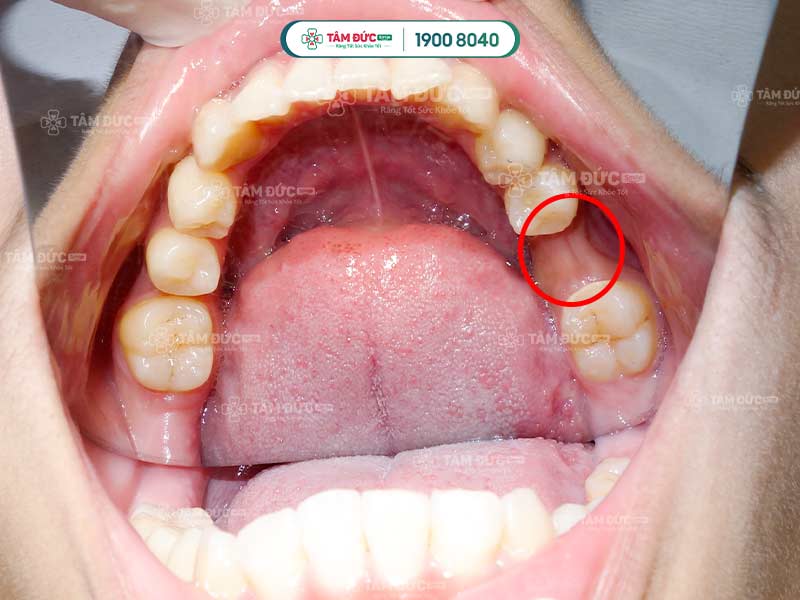

Thống kê cho thấy, tình trạng này thường xuất hiện ở các răng phía ngoài như răng nanh, răng cửa.

Ở giai đoạn đầu, tụt lợi hở chân răng phát triển một cách âm thầm nên rất khó nhận biết. Quý khách chỉ nhận ra khi mô nướu đã bị teo và phần chân răng lộ nhiều hơn. Lúc này, Quý khách có thể cảm thấy ê buốt, đau nhức và dễ bị chảy máu chân răng.

Khi mô nướu bị tụt sâu, đặc biệt là ở răng cửa, chân răng bị để lộ nhiều làm răng trông có vẻ dài hơn. Điều này rất ảnh hưởng đến thẩm mỹ nụ cười và làm Quý khách thiếu tự tin khi giao tiếp.